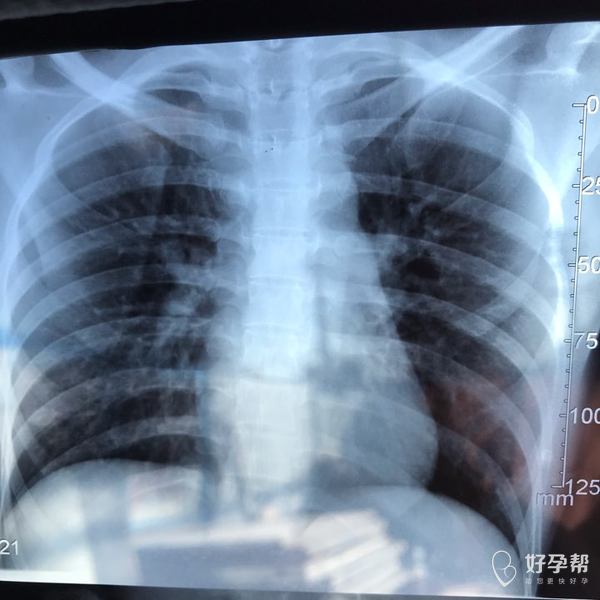

麻烦各位教授给我看看输卵管造影片子,谢谢了🙏

您好,输卵管堵塞,建议切除输卵管做试管,保守保守治疗没有多大意义,觉着我的回复对您有帮助记着帮忙点击采纳,谢谢!